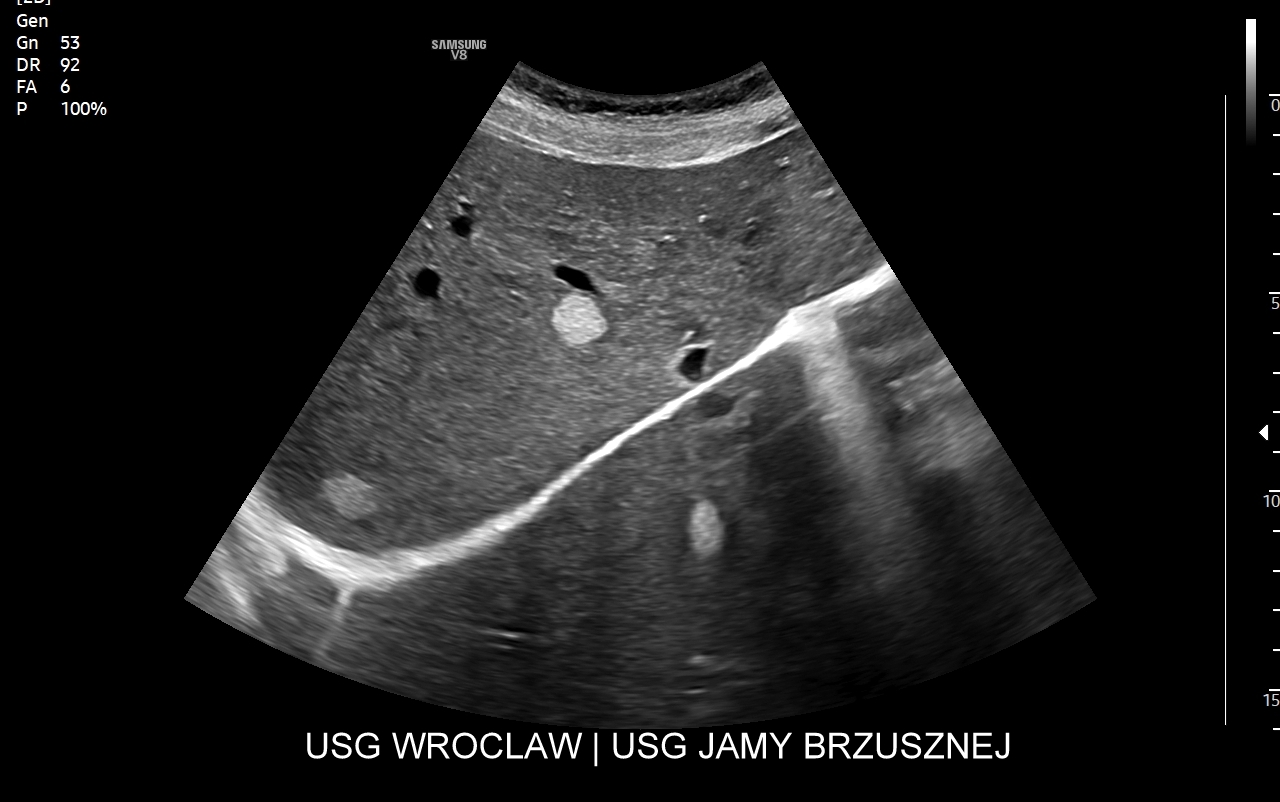

Interdyscyplinarna Pracownia USG prowadzona przez dr Tomasza Szczepańskiego dysponuje obecnie (stan na 2025 r.) najbardziej zaawansowaną platformą technologiczną do specjalistycznych badań USG we Wrocławiu i na Dolnym Śląsku w postaci aparatu Samsung V8 z rozbudowaną selekcją głowic USG dla dzieci i dorosłych oraz oprogramowaniem umożliwiającym

Dr Tomasz Szczepański zajmuje się kompleksową opieką medyczną nad swoimi Pacjentami. W ramach Interdyscyplinarnej Pracowni USG Wrocław wykonuje szereg uzupełniających się badań, zarówno klasycznych, jak USG jamy brzusznej, USG tarczycy, USG piersi, pełen zakres diagnostyki USG Doppler, jak i wysokospecjalistycznych, w tym badania multiparametryczne (MPUS), badania USG z kontrastem (CEUS), ocena przetok dializacyjnych, badania USG Doppler przepływów nerkowych, czy badania USG twarzy